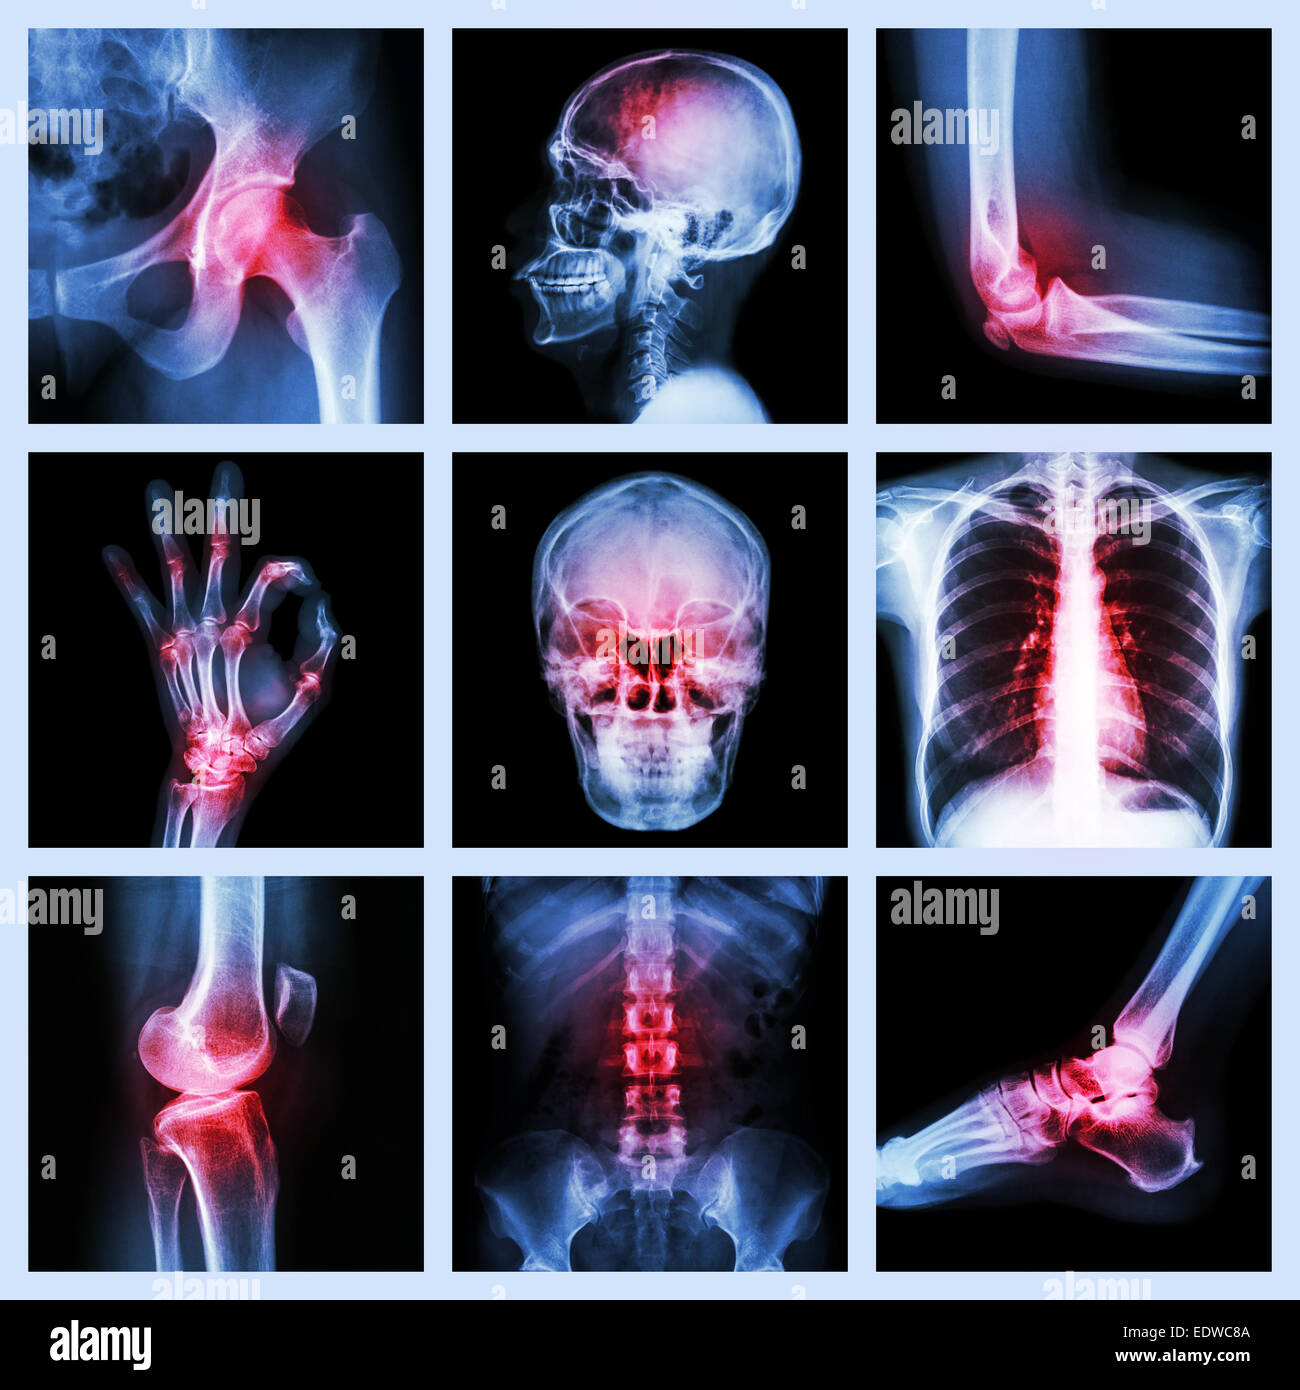

Collection X-ray et blessures multiples Banque D'Imageshttps://www.alamyimages.fr/image-license-details/?v=1https://www.alamyimages.fr/photo-image-collection-x-ray-et-blessures-multiples-77390445.html

Collection X-ray et blessures multiples Banque D'Imageshttps://www.alamyimages.fr/image-license-details/?v=1https://www.alamyimages.fr/photo-image-collection-x-ray-et-blessures-multiples-77390445.htmlRFEDWC8D–Collection X-ray et blessures multiples

Collection X-ray et blessures multiples Banque D'Imageshttps://www.alamyimages.fr/image-license-details/?v=1https://www.alamyimages.fr/photo-image-collection-x-ray-et-blessures-multiples-77390442.html

Collection X-ray et blessures multiples Banque D'Imageshttps://www.alamyimages.fr/image-license-details/?v=1https://www.alamyimages.fr/photo-image-collection-x-ray-et-blessures-multiples-77390442.htmlRFEDWC8A–Collection X-ray et blessures multiples